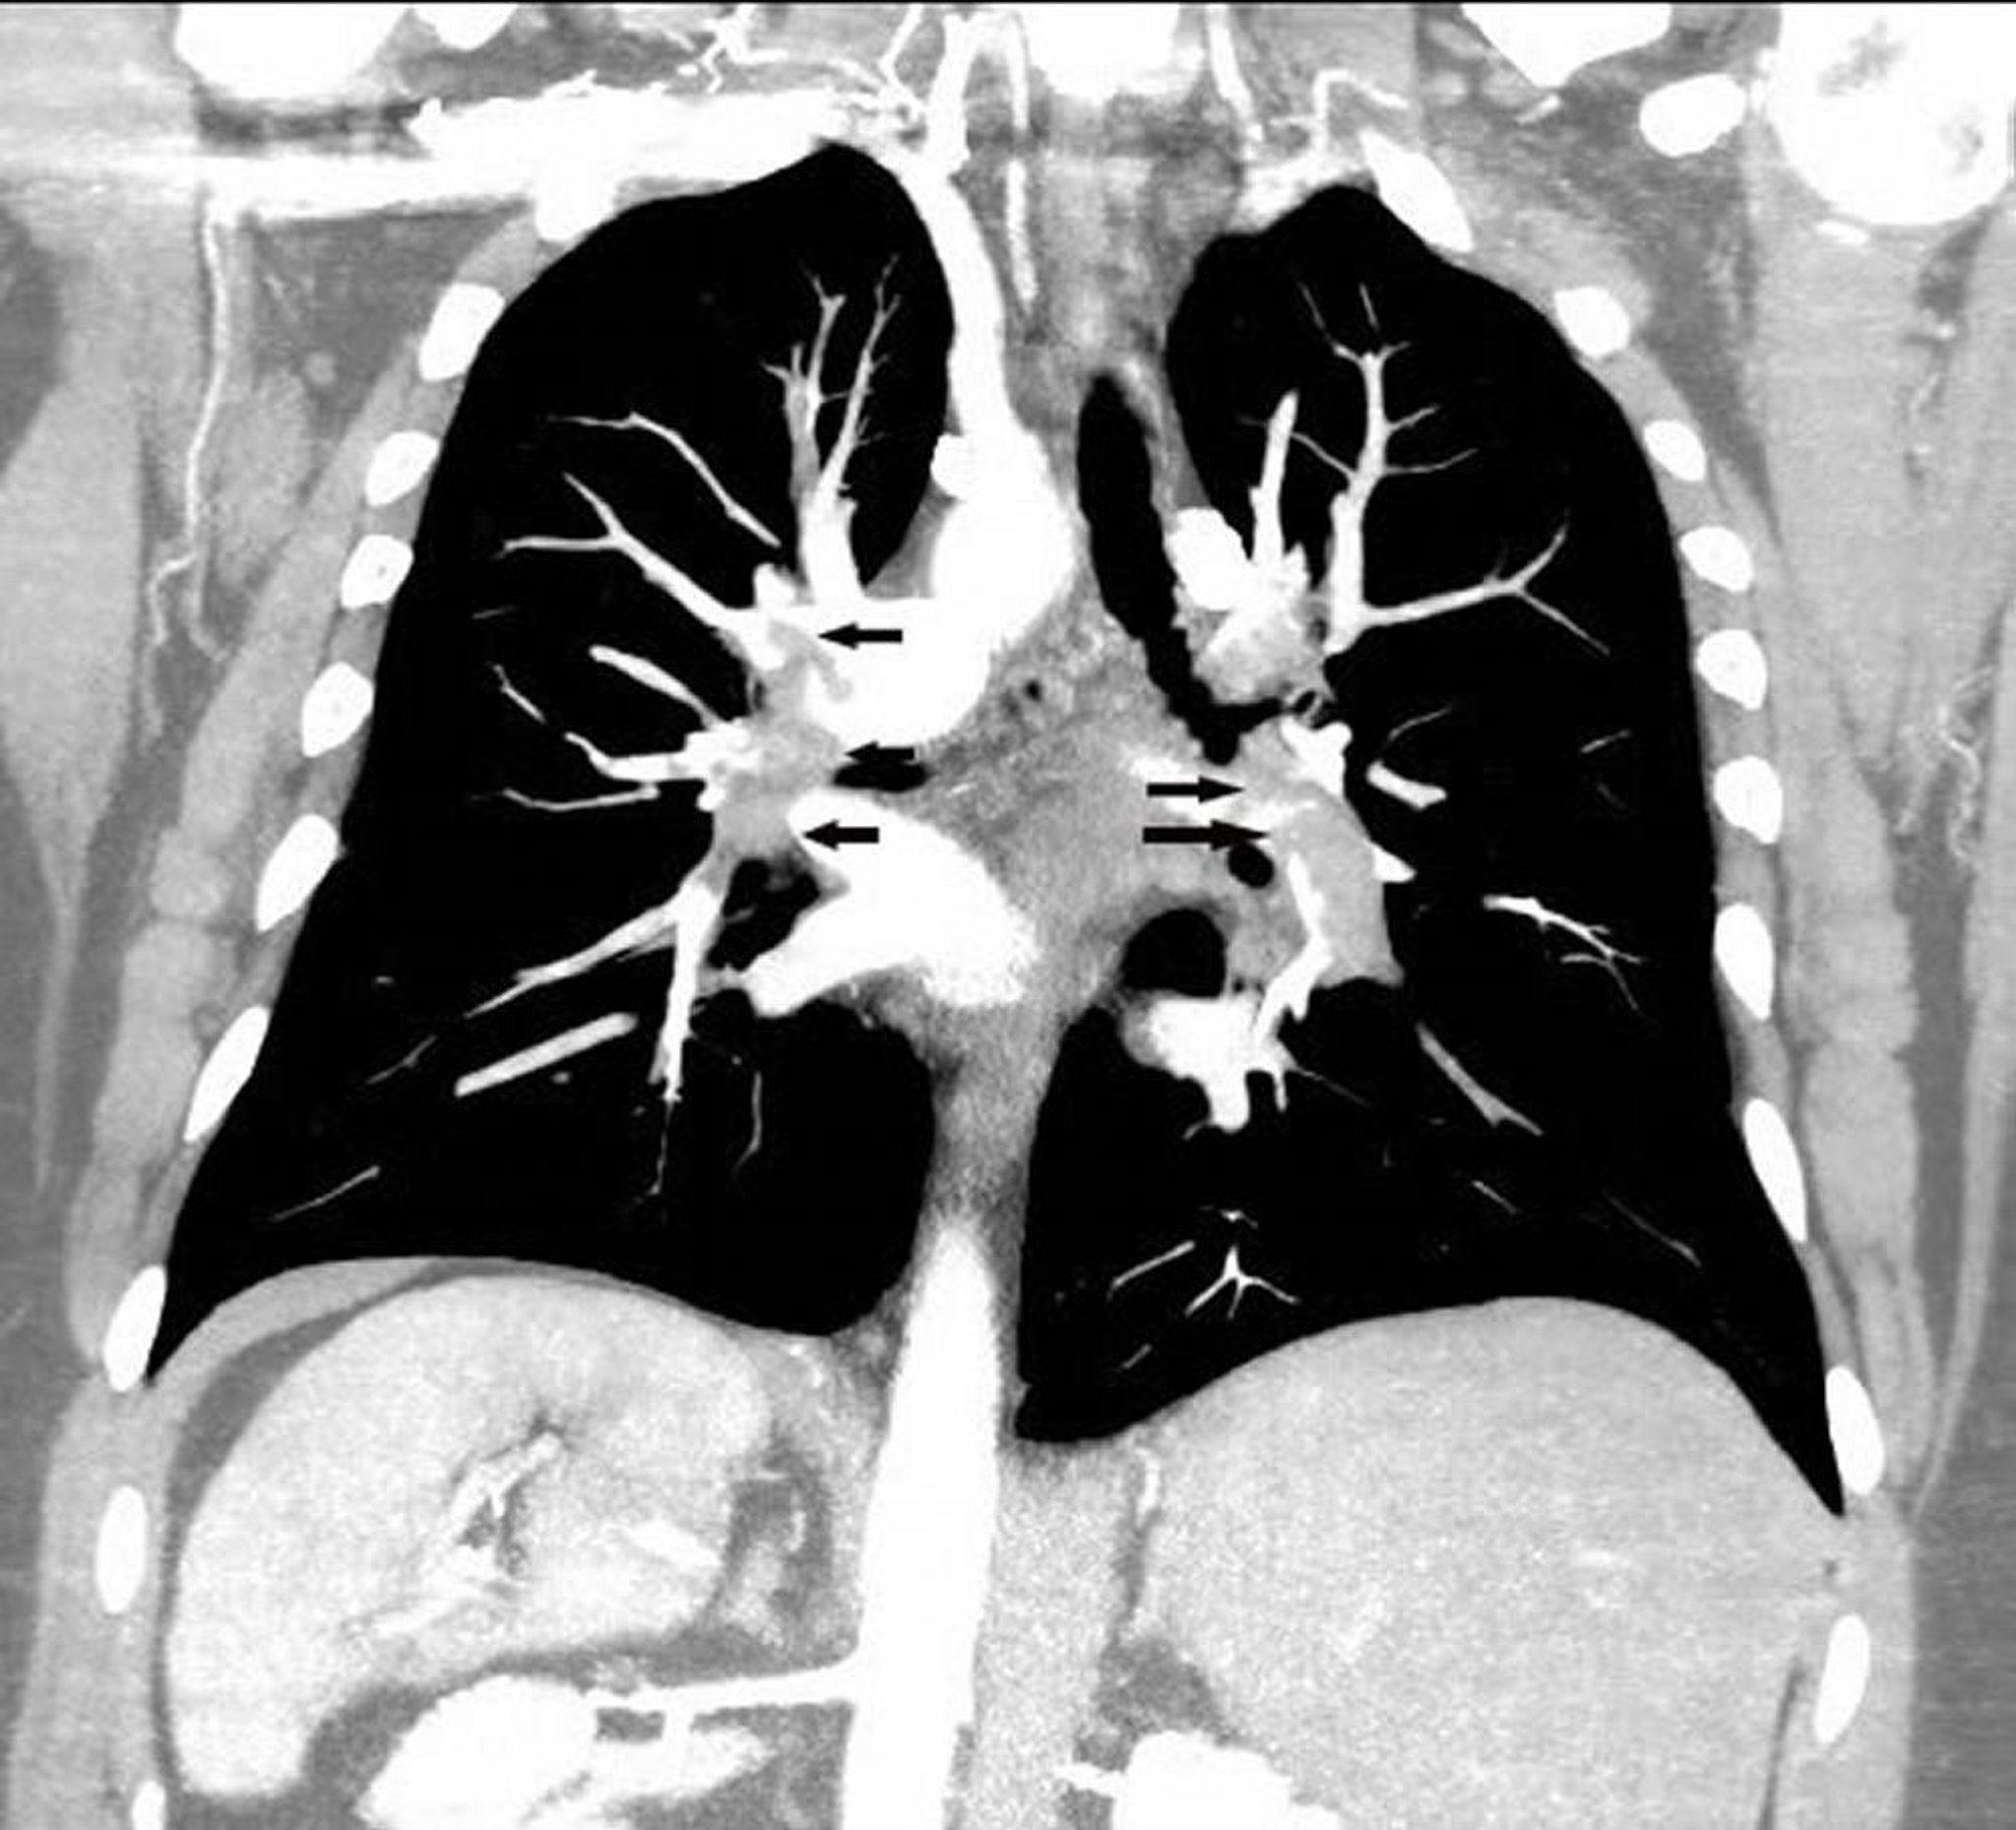

冠状断再構成のCT肺血管造影

この冠状断再構成のCT肺血管造影像では,両側の肺動脈に広範な肺塞栓(矢印)がみられる。

Image courtesy of Hakan Ilaslan, MD.